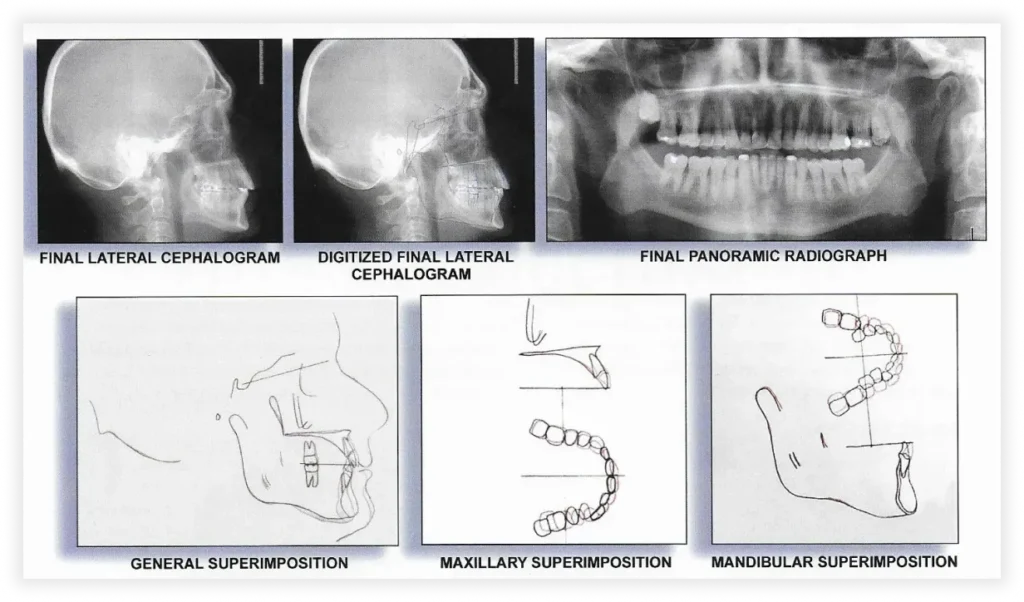

Case #1

Initial Photos

Final Photos